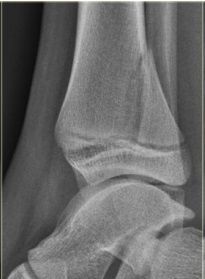

| What classification system is this? Describe the 3 classifications | Weber Ankle Fracture Classification A = Fracture below syndesmosis B = Fracture begins at joint level & extends proximally in an oblique fashion C = Fracture above the joint line |